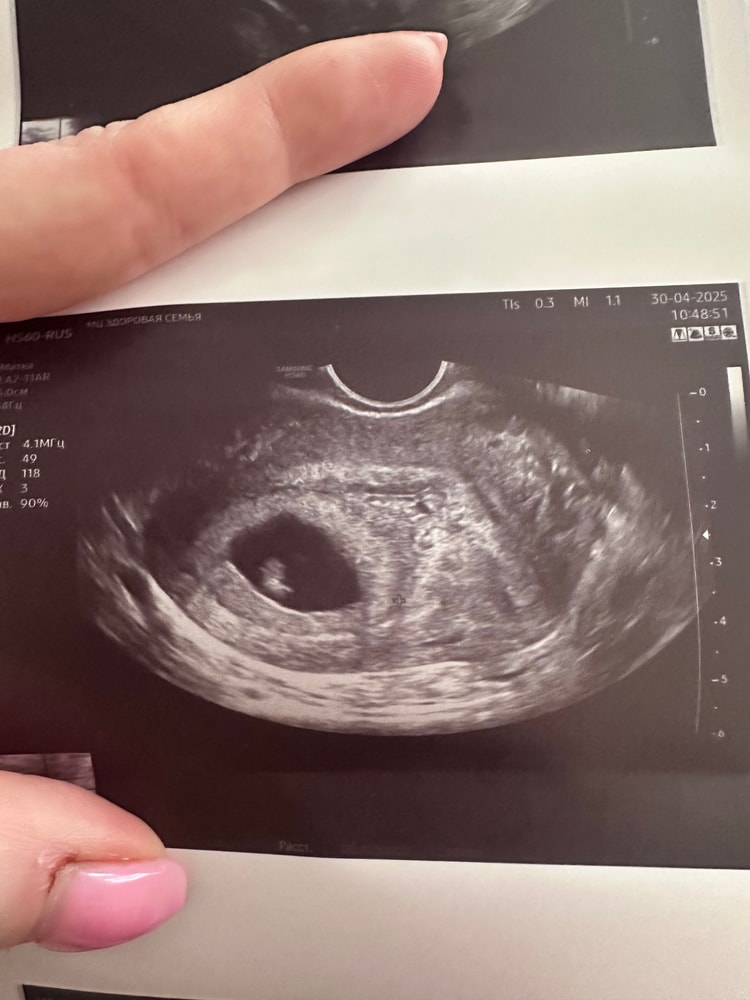

Таня,

Таня, Изображение

Лиза, мальчик ! А вы кого видите?😆

Таня, очень хочу мальчика! Надеюсь Рамзи не подведёт